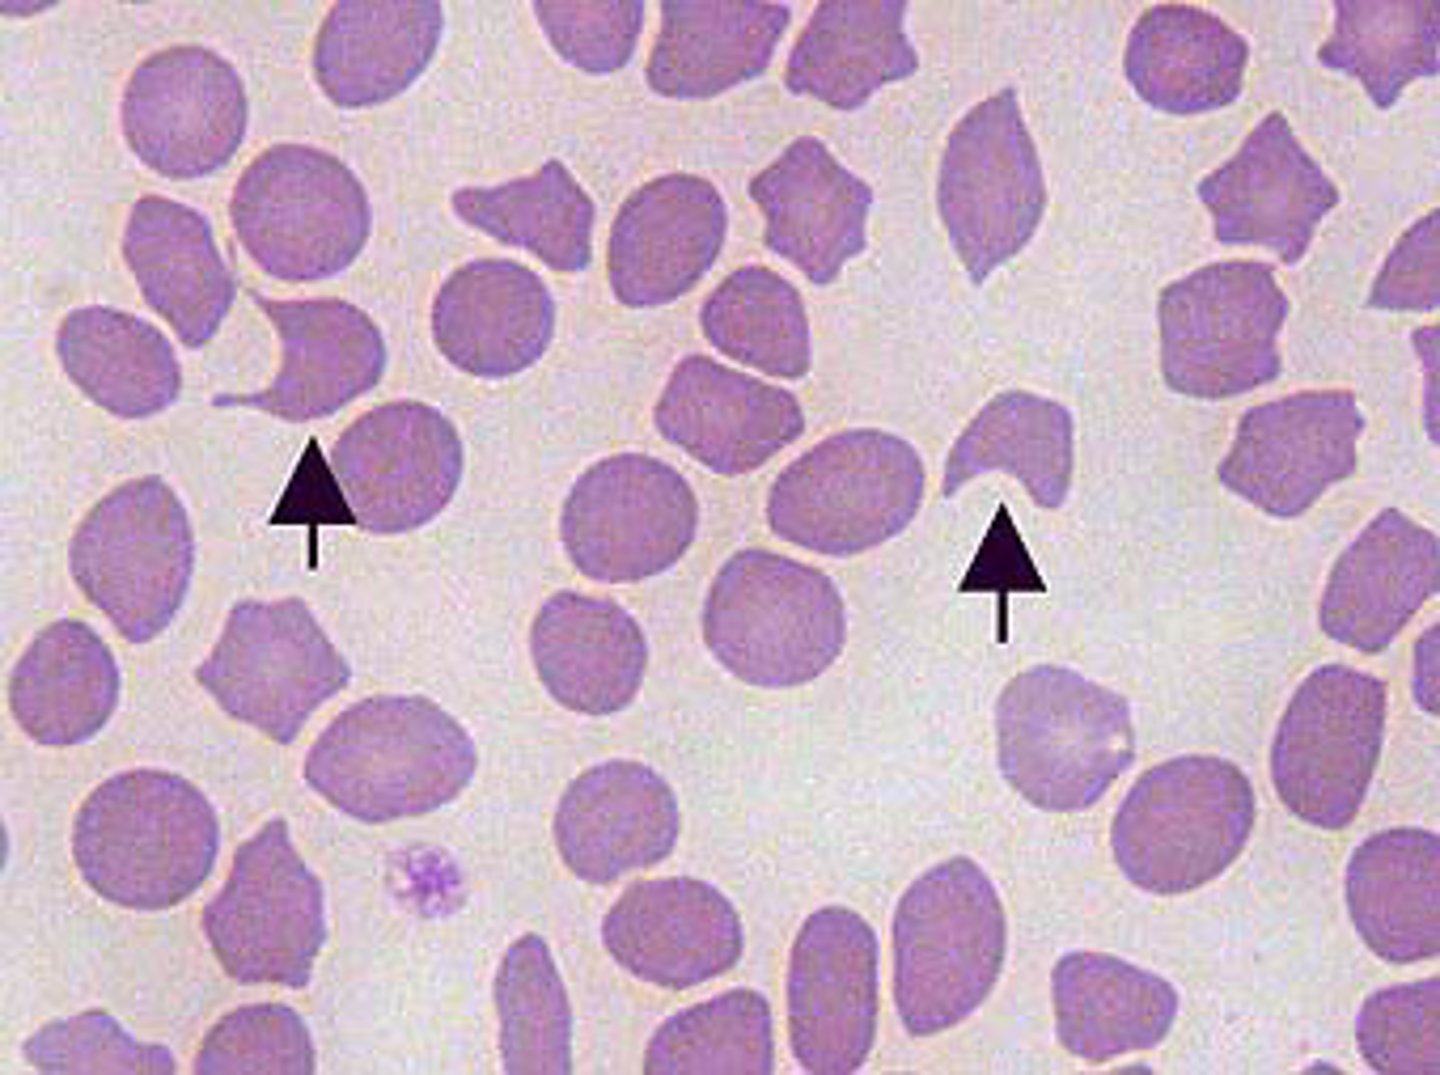

polychromasia

MAMMAL

residual RNA in cytoplasm stains the cell bluish

**reticulocytes when stained with NMB

- not in equine

anisocytosis

MAMMAL

mixture of mature and immature RBCs

- variation in RBC size

Howell-jolly body

MAMMAL

small basophilic dot typically on the periphery of the RBC

metarubricytes/ nRBC

MAMMAL

basophilic stippling

ribosomal RNA in the cytoplasm

-multiple, intracellular, blue/purple dots